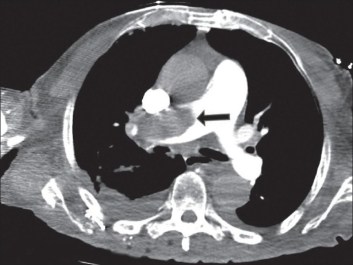

The patient has probably got a massive PE. There are several treatment options available, some more available than others depending on where you work. The RCOG suggest calling the consultant obstetrician, I would also be chatting to a respiratory consultant and getting a cardiologist to come and do an echo to look for a dilated RV (evidence of right heart strain).

(Courtesy of westjem.com)